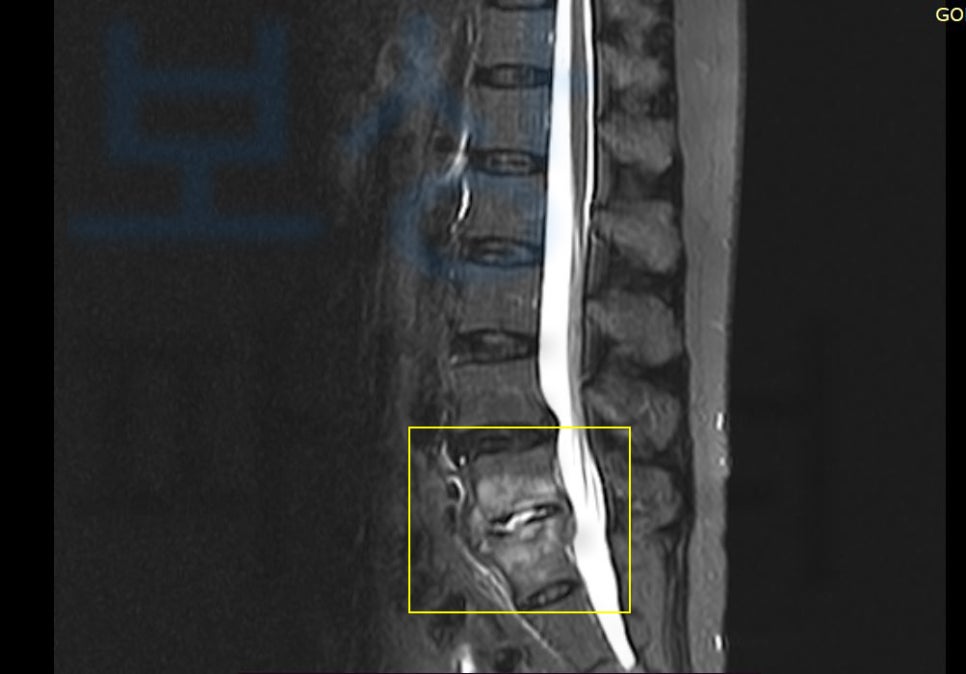

병원에서 엑스선 검사와 mri 검사 등 정밀 검사를 시행해 보니, 요추압박골절 진단을 받게 되었죠.

L5 부위의 골절 s32060 와 천골의 골절 s3210 진단을 받아 특별한 치료 없이 허리보조기 착용하며 침대에서 안정을 취하고 요양하는 보존치료를 진행하게 되었습니다.

의뢰인의 mri 검사 기록지를 보시면

Acute compression fracture, L5, S1 즉 급성 척추압박골절 요추 5번, 천추 1번 진단을 받았습니다. 보험 약관에 보시면 보험사에서 인정하는 척추 장해 부위는 경추에서 흉추, 요추, 제 1천추까지 입니다.

“척추체”의 압박골절만 해당되며 그 외 극돌기, 횡돌기, 갈비뼈 혹은 미추 즉 꼬리뼈골절은 최근 개정된 약관 기준으로 척추의 장해에 해당하지 않습니다.